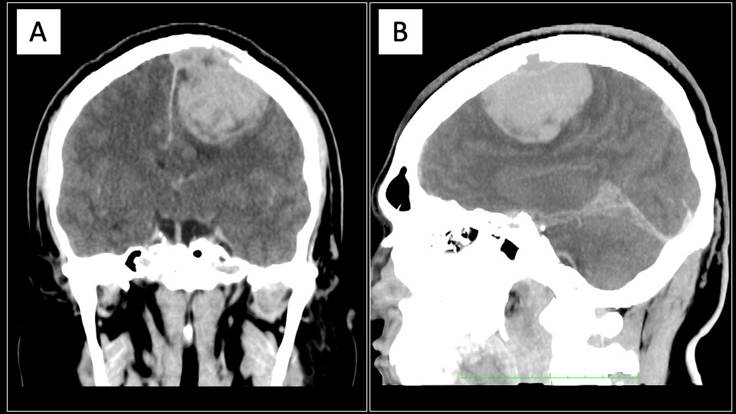

Se completa protocolo diagnóstico por el servicio de neurocirugía con tomografía de cráneo, evidenciando una imagen heterogénea de predominio hiperdenso, con halo hipodenso, con dimensiones máximas de 60x48x40 mm en sus ejes, con un volumen calculado de 60.1 cm3 en región parasagital frontal izquierda, la cual refuerza a la administración de contraste, Estructuras de la línea media con desplazamiento de izquierda a derecha de 6.9 mm secundario a efecto volumétrico de la lesión ya descrita, además de lesiones líticas en hueso frontal izquierdo y parietal ipsilateral (Figura 2).

A. Corte coronal; B. Corte sagital.

Figura 2 Metástasis a cerebro de liposarcoma mixoide (tomografía de cráneo)